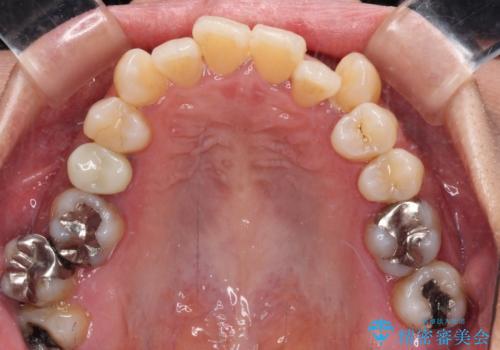

- 前歯のデコボコや八重歯を治したいとのことで来院された患者様です。

受け口傾向の骨格であり、前歯はクロスバイトまたは切端咬合となっており、下顎を中心に歯列全体の後方移動を行い、IPR(歯と歯の間を削る)によってデコボコが解消するように設計し、インビザラインにより治療を行うこととしました。

受け口傾向のインビザライン矯正は比較的治療を行いやすいため、きれいに仕上げることができました。舌の突出癖が顕著であったため、改善のためのトレーニングをしっかりと行っていただきました。